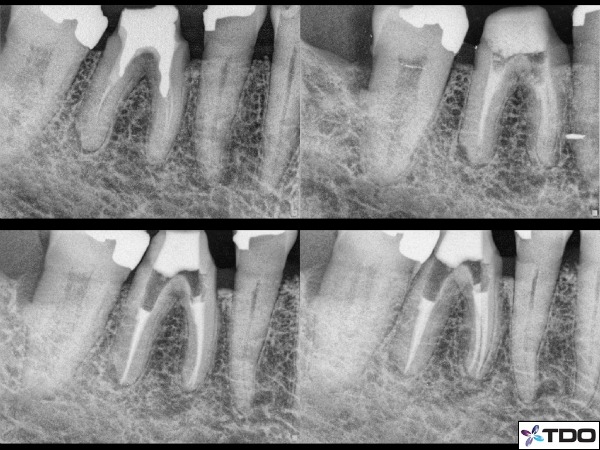

Retreatment endodontic cases are perhaps an even more useful to prove the importance of the multi-visit approach. Retreatment cases are generally more complex. There are posts (all types), missed canals, various materials in the canals (silver points, thermafil, gutta percha, files, etc) all of which take a lot of time and effort and skill to remove.

Figure 2: Here is a retreatment case from Adam Monroe in which a multi-visit (3) process was critical based on the difficulty of removing the amalgam posts in the canals. He also needed to properly shape the canals to the terminus and build the coronal tooth with composite for better protection and stability. The upper left shows the pre-operative condition. Upper right is with the coronal build-up in place and Ca(OH)2 in the canals. The bottom x-rays show two immediate post-operative pictures with a temporary filling in the access point.